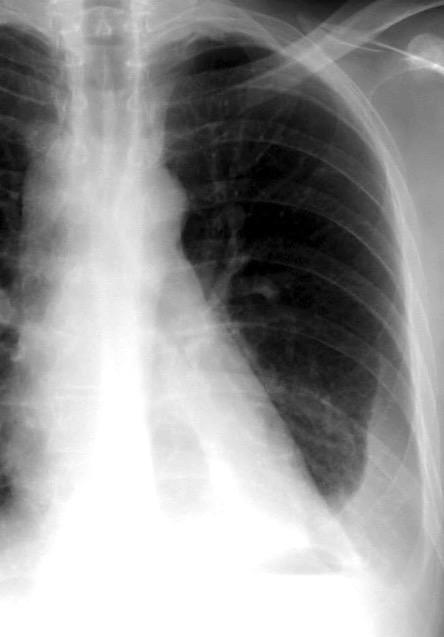

Neumonía a neumococos base izda. con derrame que aumenta.

Broncograma en lateral y en US.

(36-66% en ingresados)